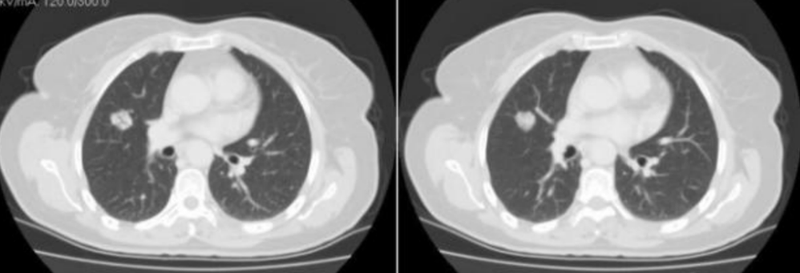

空泡征

空泡征是一个非常熟悉的名词了,这一征象指病灶内  1-2mm(或<5mm) 的点状透亮影,单个或多个,也主要见于早期肺癌,其病理基础主要是 尚未被肿瘤破坏、替代的肺结构支架如肺泡、扩展扭曲的未闭细支气管等,部分是肿瘤坏死腔、含粘液的腺腔结构以及乳头状癌结构间的含气间隙。此外上包括未被肿瘤占据的含气肺组织及未闭合的或扩张的小支气管。此征主要见于细支气管肺泡癌和腺癌,也可见于鳞癌。肺窗下观察为小泡状模糊低密度灶,纵隔窗为小泡状透亮影。

空泡征虽然是非常熟悉的名词,但在这里还是要重复叙述,目的有三: 第一、进一步了解该征的病理基础; 第二 、搞清楚空泡征和空洞及支气 管充气征的差别。病理基础上边已经简单谈及,那么空泡征和空洞的区别是什么?按照空泡征的定义,病灶直径5mm以内,大于5mm考虑是空洞,反之就是空泡征。支气管充气征是见于连续多个层面,直达结节外缘。